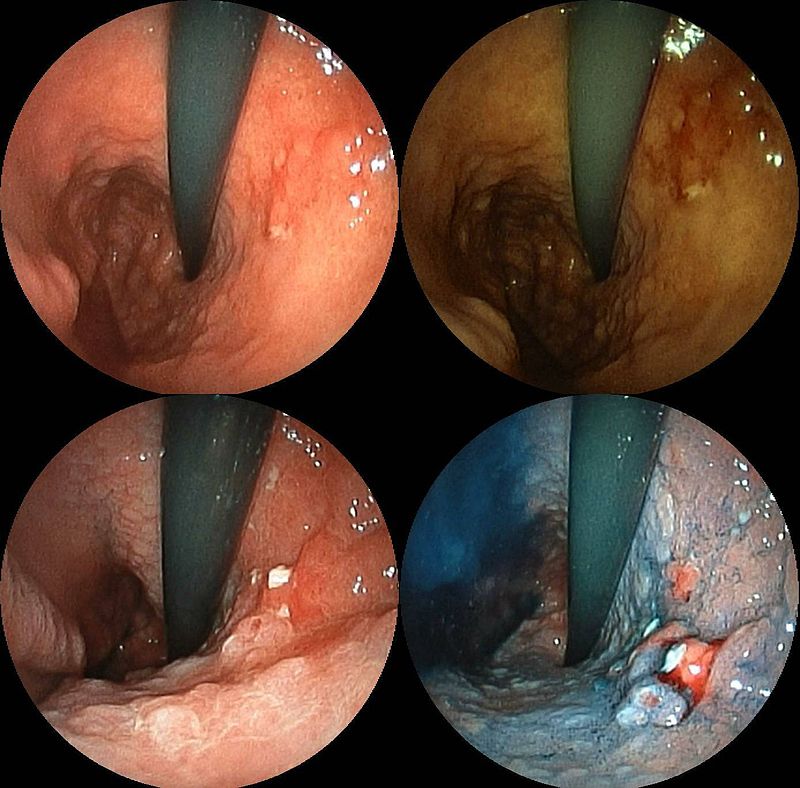

Peptic Ulcer Disease

Peptic ulcer disease is a mucosal ulcer of the gastrointestinal tract.

Peptic ulcer disease commonly involves the proximal duodenum (90 percent) or distal stomach (10 percent).

Causes of peptic ulcer diseases include:

- H. pylori is nearly often the cause of duodenal ulcers (> 95 percent)

- Zollinger Ellison (ZE) disease occasionally

- Non-steroidal anti-inflammatory (NSAID) medications

- Bile reflux

Peptic ulcer disease presents with epigastric pain that gets better with food.

Endoscopic diagnostic biopsies reveal Brunner gland hyperplasia and ulceration if the duodenum is involved.

Peptic ulcers may rupture, resulting in acute pancreatitis or anterior ulcer bleeding from the gastroduodenal artery (posterior ulcer).

The smaller curvature of the antrum is where an ulcer is most frequently found.

The left stomach artery may bleed during a rupture.

The majority of benign peptic ulcers are small (less than 3 cm), well defined, and encircled by radiating folds of mucosa.

Nearly seldom are duodenal ulcers cancerous (duodenal carcinoma is extremely rare).

Carcinoma is a differential diagnosis for peptic ulcers.

Gastric cancer can result in stomach peptic ulcers (intestinal subtype).

Malignant ulcers are big, asymmetrical, and have piled-up margins.

Biopsy is needed for definitive diagnosis.